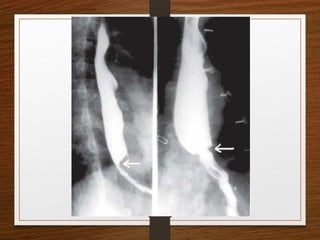

Doubt about the

diagnosis on the plain

radiographs

Contrast enema

• Features seen at the point of torsion include a

smooth, curved tapering of the colonic lumen, like a

hooked beak (the bird of prey sign)

• the mucosal folds often show a ‘screw’ pattern at the

point of twist

Doubt about the diagnosison the plain radiographs Contrast enema

• 33.

Contrast enema • Featuresseen at the point of torsion include a smooth, curved tapering of the colonic lumen, like a hooked beak (the bird of prey sign) • the mucosal folds often show a ‘screw’ pattern at the point of twist